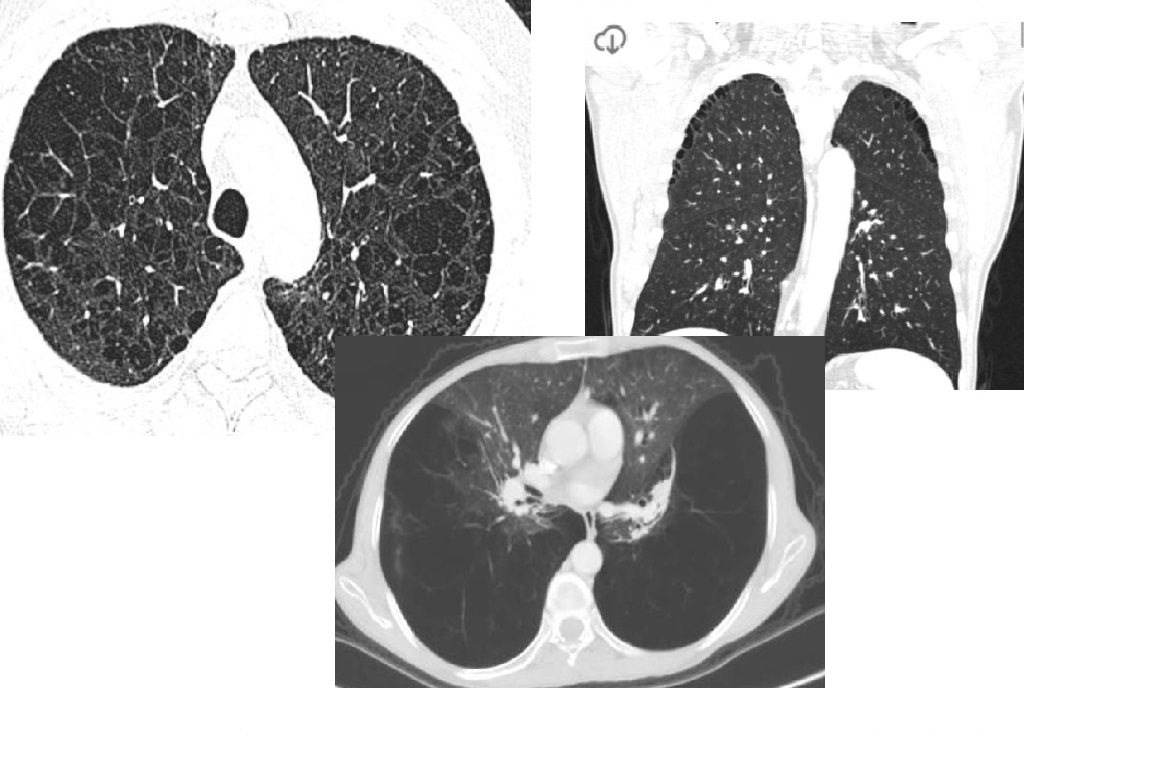

Lymphangioleiomyomatosis (LAM)

Diffuse no lobe predominant Thin walled cysts

Spontaneous PTX

Premenopausal women

NORMAL lung volumes

Chylous pleural effusions

increased lung volumes

Associated with tuberous sclerosis - 1/3rd have AMLs